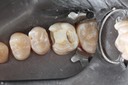

Gary Umeda #18,19,20 pre-op

Gary Umeda #18, 19, 20 prep